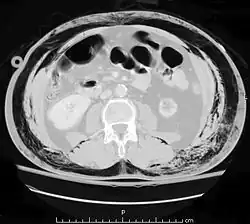

El intestino delgado ocupa gran parte del abdomen y puede resultar dañado en lesiones penetrantes.[3] El intestino puede resultar perforado, y la presencia de gas en la cavidad abdominal visualizada en una tomografía axial computarizada se interpreta como un signo diagnóstico de perforación intestinal.[4] Sin embargo, la presencia de aire en la cavidad intra-abdominal también puede ser por causa de neumotórax—aire en la cavidad pleural fuera de los pulmones que se ha escapado de las vías respiratorias—o neumomediastino—aire en el mediastino, el centro de la cavidad torácica—.[4] Una lesión intestinal puede estar asociada con complicaciones tales como infección, absceso, obstrucción intestinal, y la formación de fístulas. La perforación intestinal debe ser reparada quirúrgicamente.[4]

La ecografía puede detectar fluidos como la sangre o contenido gastrointestinal en la cavidad abdominal y es un procedimiento no invasivo y relativamente seguro para el paciente.[4] La tomografía computarizada de exploración es la técnica preferida para las personas que no están en riesgo inmediato de choque,[13] pero ya que la ecografía se puede realizar en una sala de emergencia, este último se recomienda para personas que no están lo suficientemente estables como para pasar al tomógrafo.[1] Sin embargo, los pacientes con traumatismo abdominal con frecuencia necesitan la tomografía computarizada para otros traumatismos concomitantes, por ejemplo, cráneo o tórax. En estos casos, la TAC abdominal se puede realizar al mismo tiempo, sin perder tiempo en la atención de los pacientes.[4]